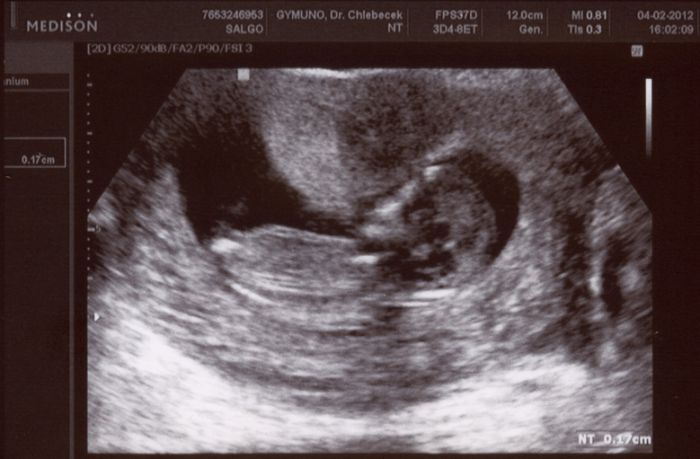

Jinak dneska jsem ve 13+4 a už mám vybranou porodnici. V Praze se musí ve 14+0 registrovat. Budu rodit na Bulovce, už to mám zařízený ;-) ...mám tam tak trošku protekci ;-)

Jo a ještě vám sem hodím fotečku našeho ufounka z pátku, kdy mu bylo 12+4.